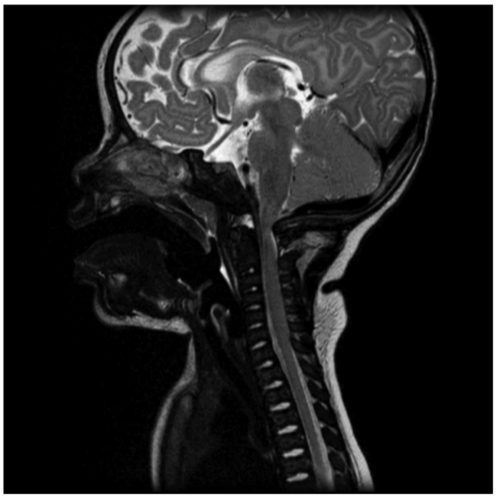

Developmental motor delay is also associated with unresolved thoracolumbar kyphoscoliosis. It is recommended that patients with kyphotic curves between 20 and 40 degrees be monitored for progressive deformity and symptoms of spinal cord compression. As the child begins to stand and walk, lumbosacral hyperlordosis may become apparent. This additional deformity is likely due to excessive anterior pelvic tilt in these children while standing.5 - Foramen magnum stenosis is the first spinal manifestation in an infant with achondroplasia (Figure 3). Common presenting symptoms include respiratory difficulty, excessive snoring, or apnea. Other symptoms that can present are apnea, lower cranial nerve dysfunction, difficulty swallowing, hyperreflexia, hypotonia, weakness/paresis, and clonus.5

Figure 3. Foramen magnum stenosis with significant compression of the cervicomedullary junction. Gaillard F, Walizai T, Ranchod A, et al. Achondroplasia. Reference article, Radiopaedia.org. Accessed on 24 Sep 2025. Link